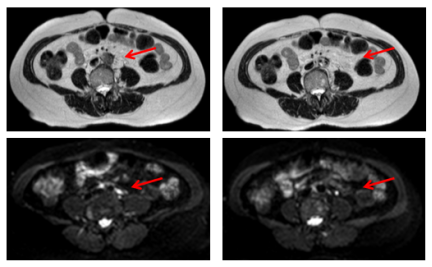

image.png 图4 疗效评价

化疗12周期后胸部评价:2024-04-01胸部CT:右肺下叶背段(Se4 In108)钙化结节同前。左肺上叶前段、下叶外基底段、右肺(In75 167 183)见数个微小结节同前,建议随访。

image.png

图5 化疗12周期后胸部评价

化疗12周期后腹膜后评价:2024-04-01腹膜后淋巴结情况:下腹部腹膜后至双侧髂血管起始段旁淋巴结较前明显缩小,较大者约16mm×9mm(初始约36mm×22m),未见新增病灶。

image.png 图6 化疗12周期后腹膜后评价